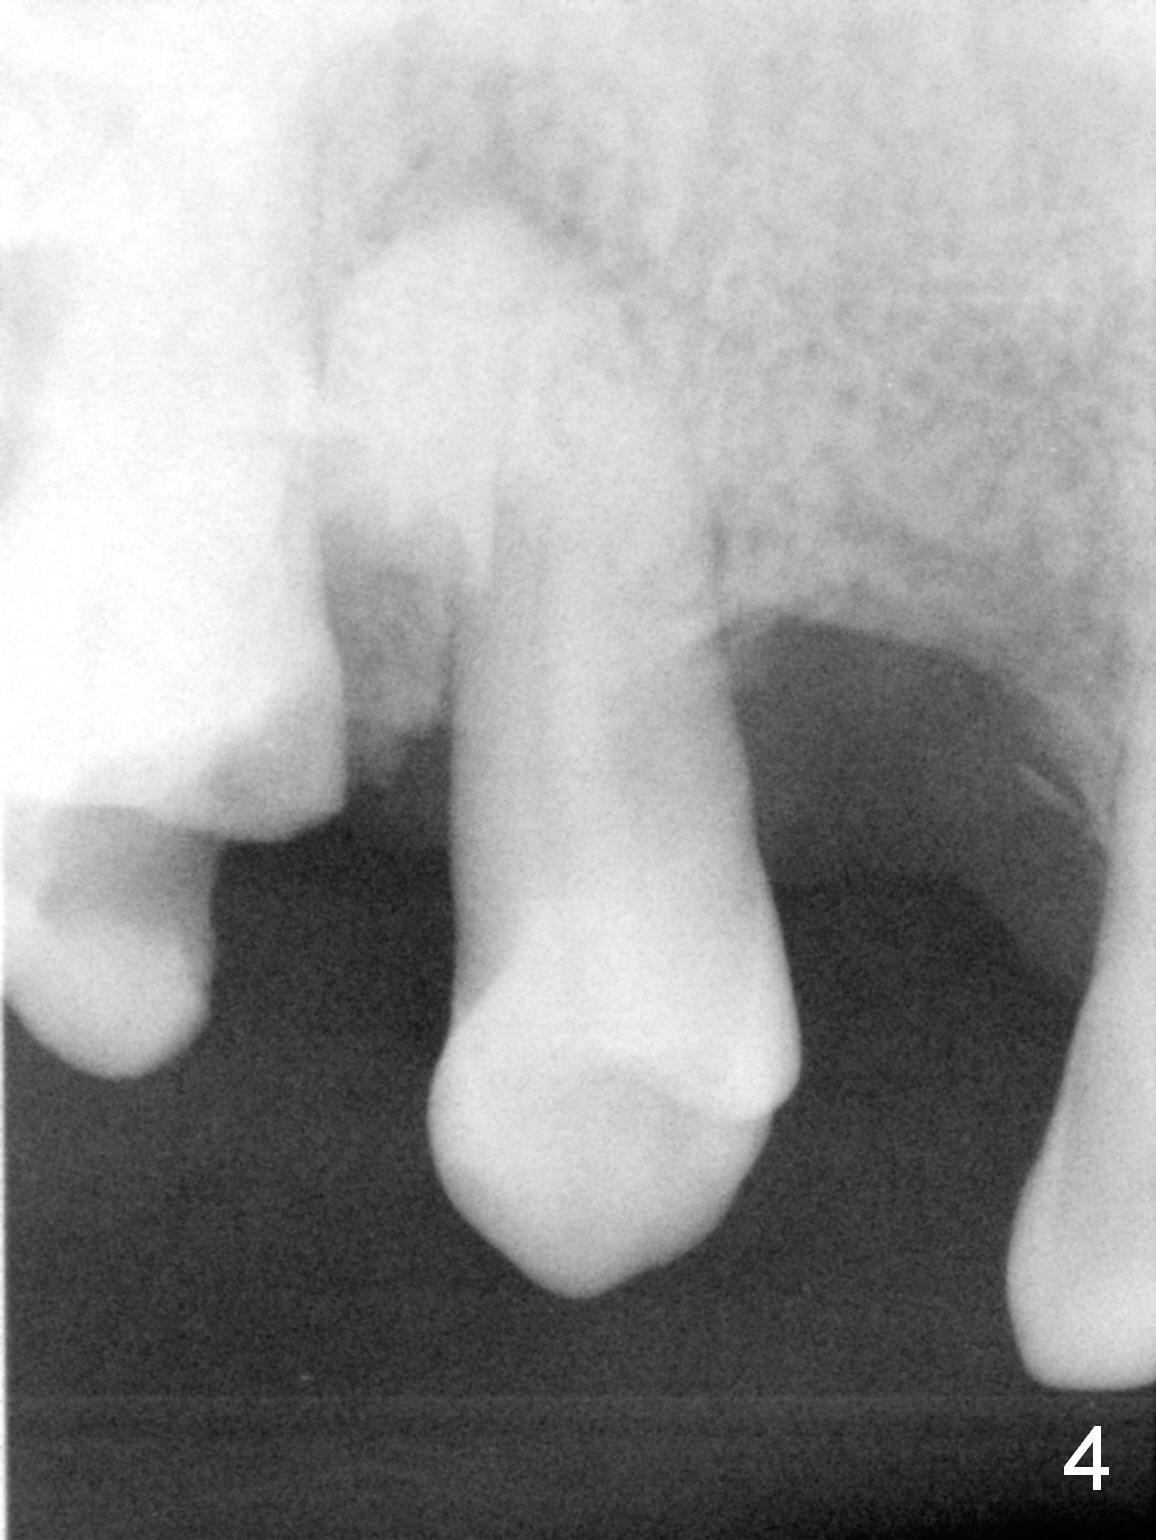

A 62-year-old man (CZ) has had chronic periodontitis. A month ago, five immediate implants were placed in the lower anterior region. Fig. 1 shows a PA taken 4 years ago: #4 residual root and #6 severe bone loss. A 4.1x14 mm bone-level implant is planned immediately after extraction (Fig.2). Clinically, the residual root is oval in shape (Fig.3 dashed line). The implant is placed as palatal as possible after socket treatment with 2% Xylocaine/1:50,000 Epinephrine (Fig.4). In addition, the osteotomy may have to be established in the distal wall, since the root tip tilts mesially (Fig.1). Take the 1st intraop PA after 2 mm pilot drill.